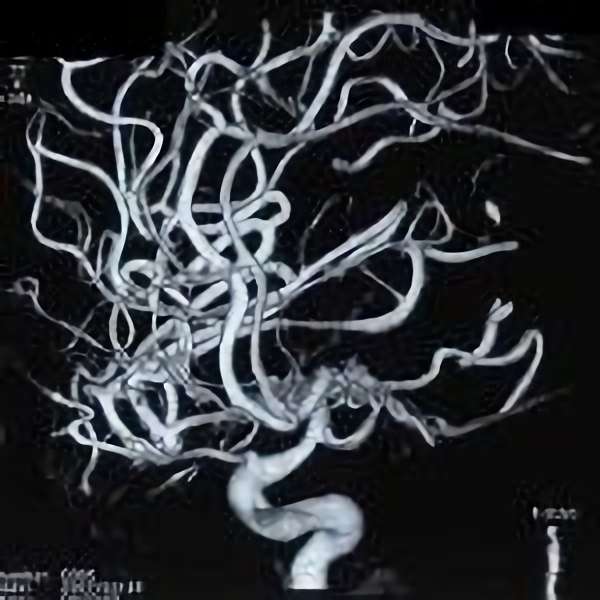

脳血管撮影

手術前

手術後